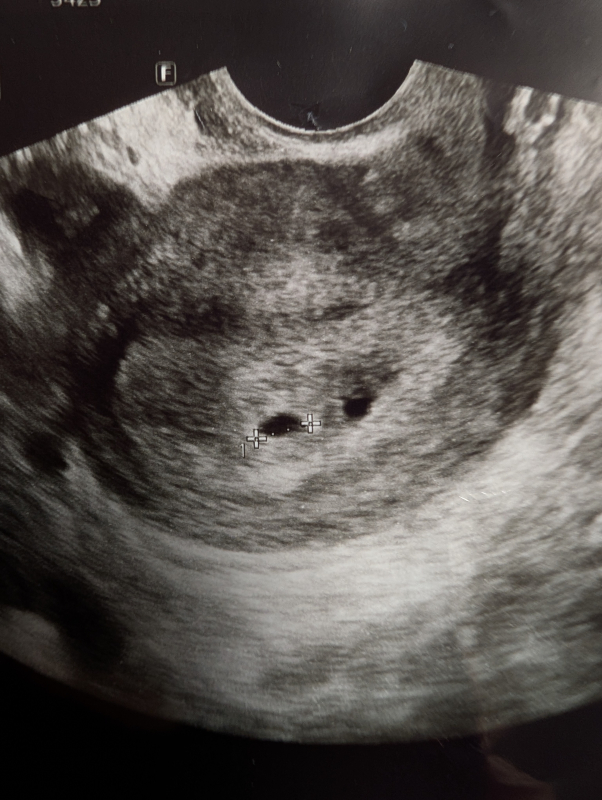

妊娠5週頃のエコー写真についてご相談です。

診察していただいた先生からは5mmで

順調に育っているとのお話のみでしたが

エコー写真を見返した際、測定した黒丸の右横にも

同じような黒丸がありこれはなんなのかと心配になりました。

妊娠初期のエコーで、黒い点が2つあったことがご心配なのですね。

胎嚢の近くにもう一つ黒い点が見られるのですね。実際にエコーを拝見していませんので、はっきりとしたことは明言できませんが、可能性として考えられるのは、出血のこともありますし、粘膜の塊などがそのように見えることもあります。また、おっしゃるように、双子の可能性もあると思います。

ですが、医師からは特に何も指摘がなかったということであれば、出血や双子ではない可能性が高いように思いますよ。粘膜の塊などが黒っぽく見えることもありますので、何も言われていないのであれば、そのようなものなのかもしれませんね。